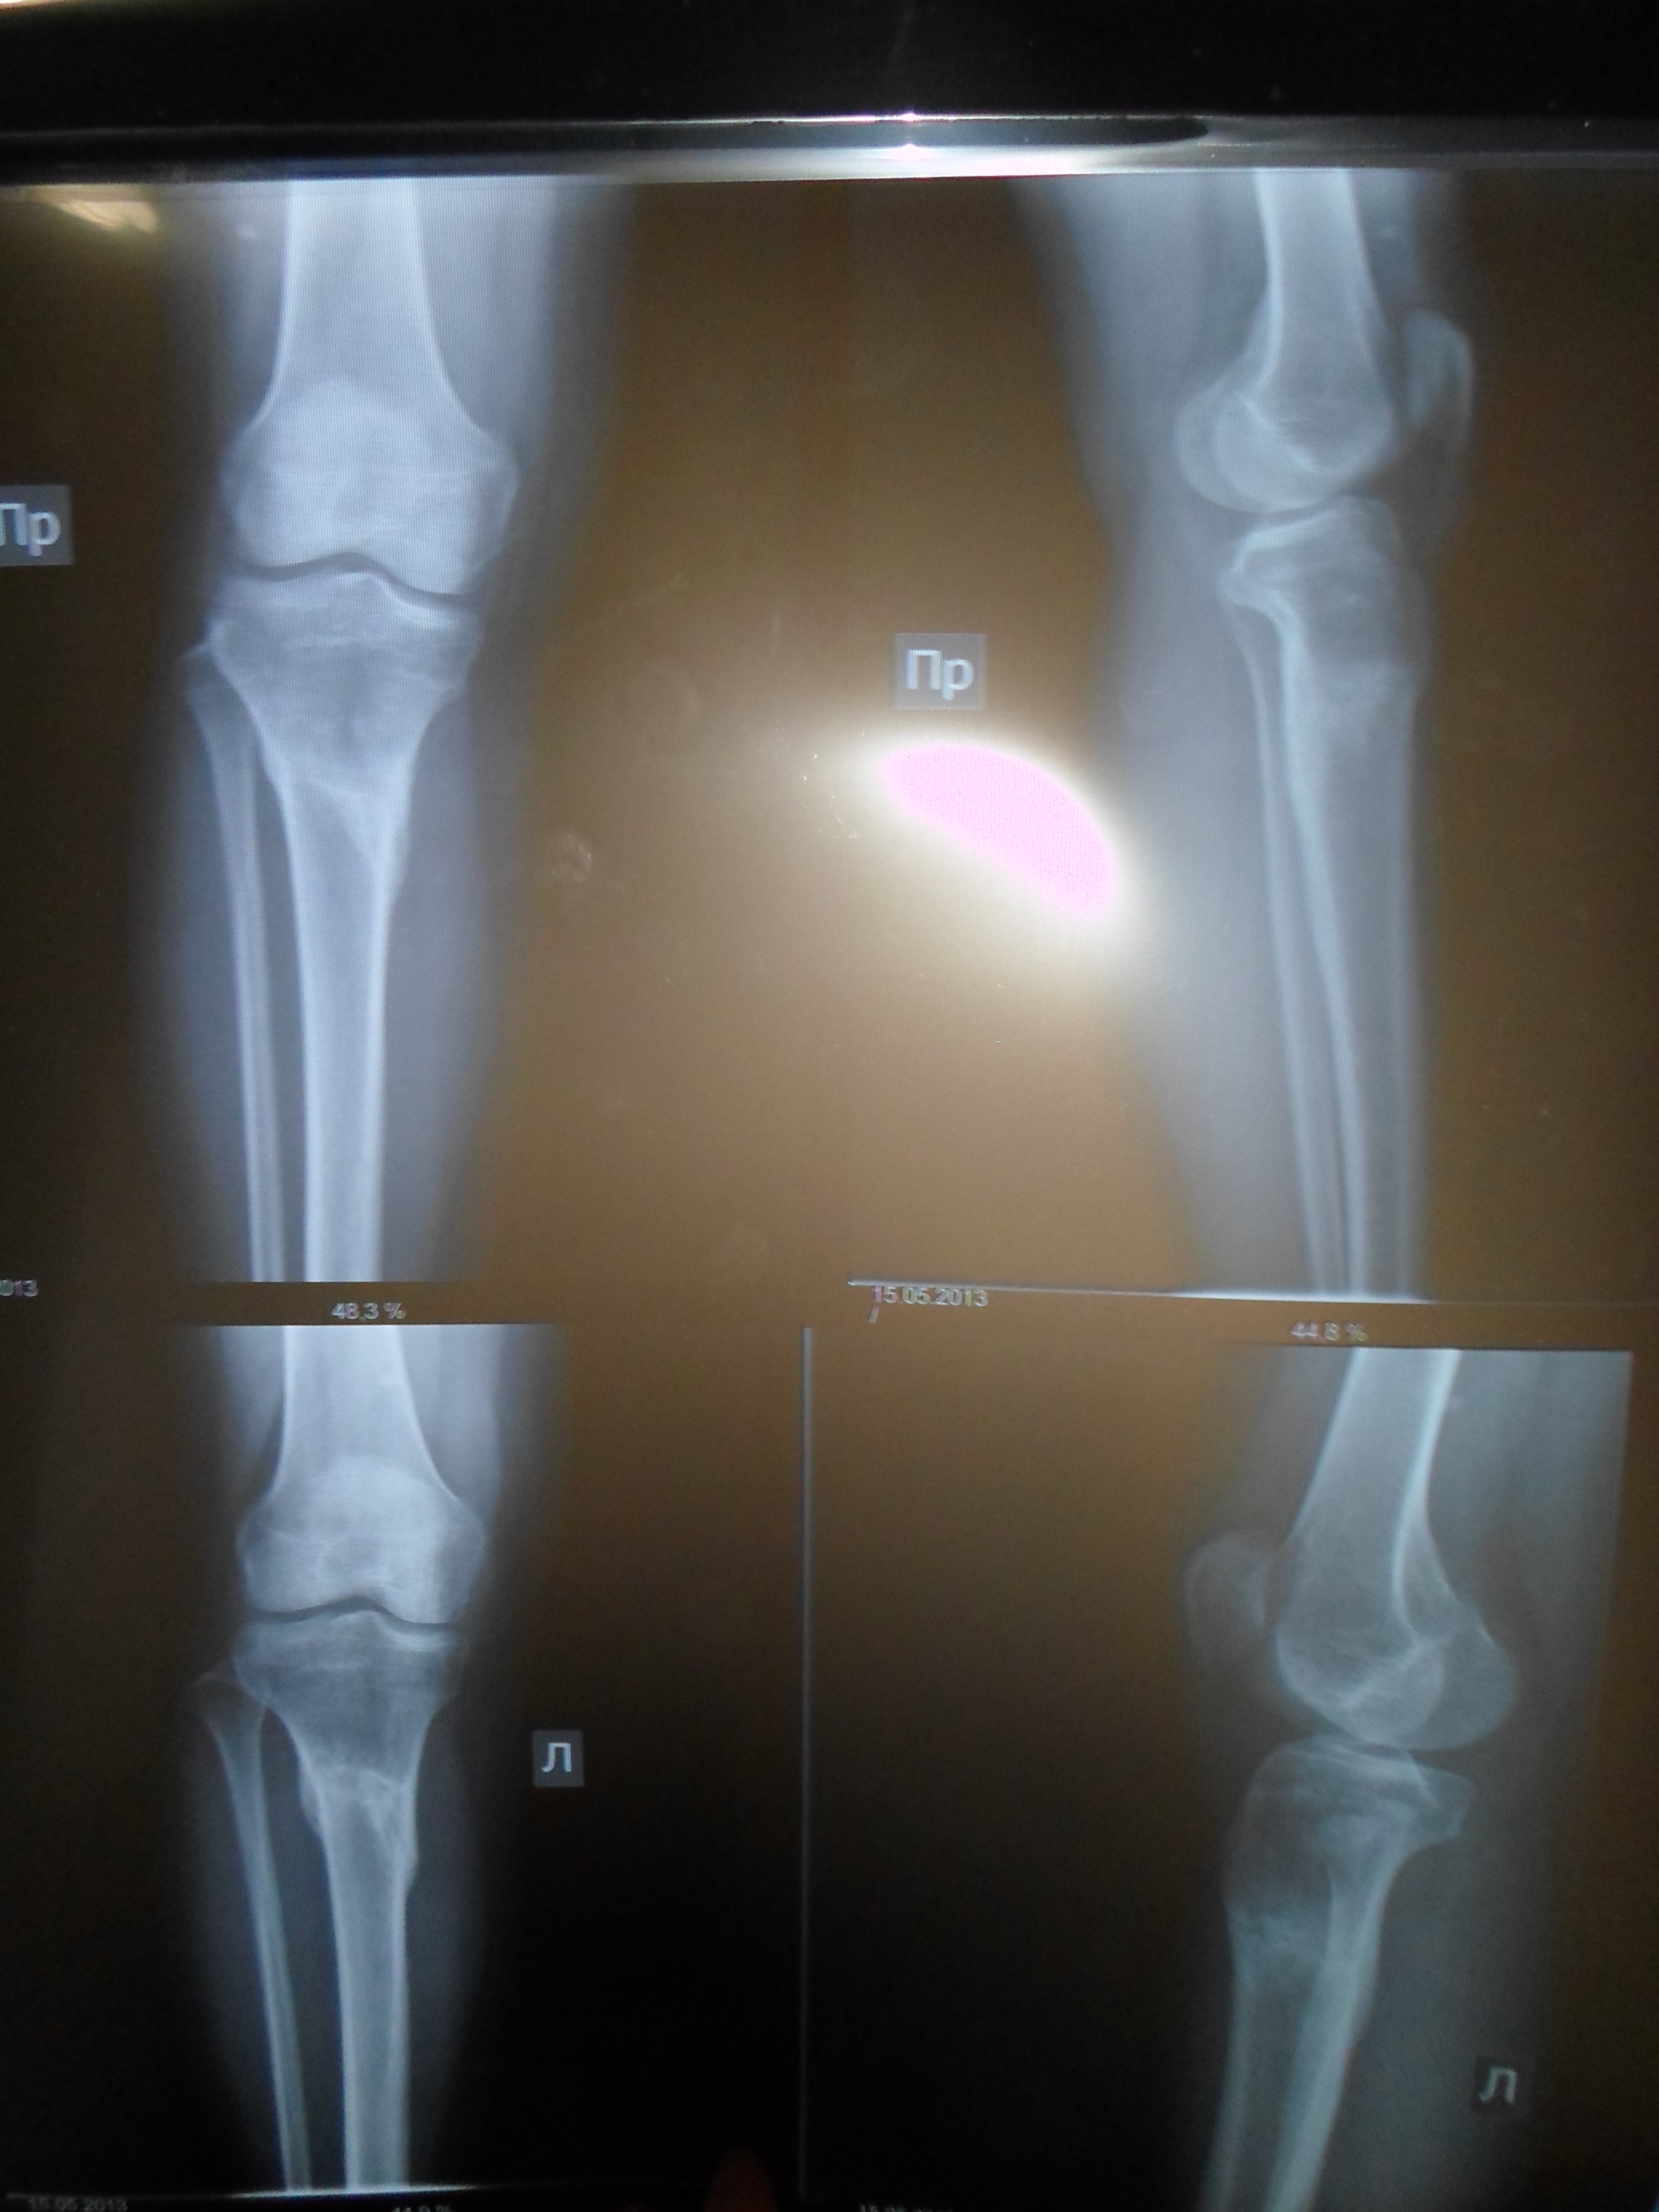

Я проподала тут некоторое время , лежала в больнице с осложнением после гриппа, уже дома.Вчера сделала фото ног , через 2 недели после снятия, зацените.

- Диагноз: О- образная деформация нижних конечностей